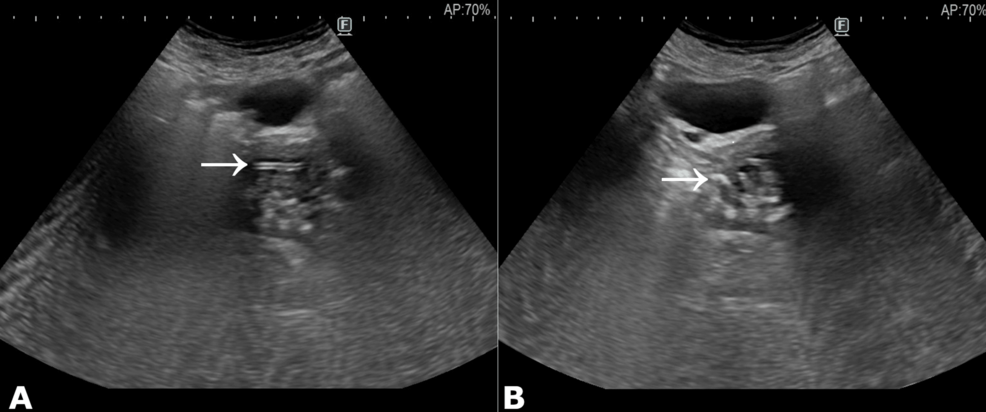

The future of preventing these complications lies in advancements in imaging technology and the integration of artificial intelligence (AI). Traditional imaging methods, like ultrasound, can sometimes struggle to reliably identify older IUDs, particularly those that have migrated or become partially embedded in the uterine wall. However, newer techniques offer promising solutions.

High-resolution ultrasound, coupled with saline infusion sonography (SIS), can significantly improve IUD visualization. SIS involves injecting sterile saline into the uterine cavity, distending it and providing a clearer view of the uterine lining and any retained devices. This technique is becoming increasingly accessible and is a relatively low-cost, non-invasive option.